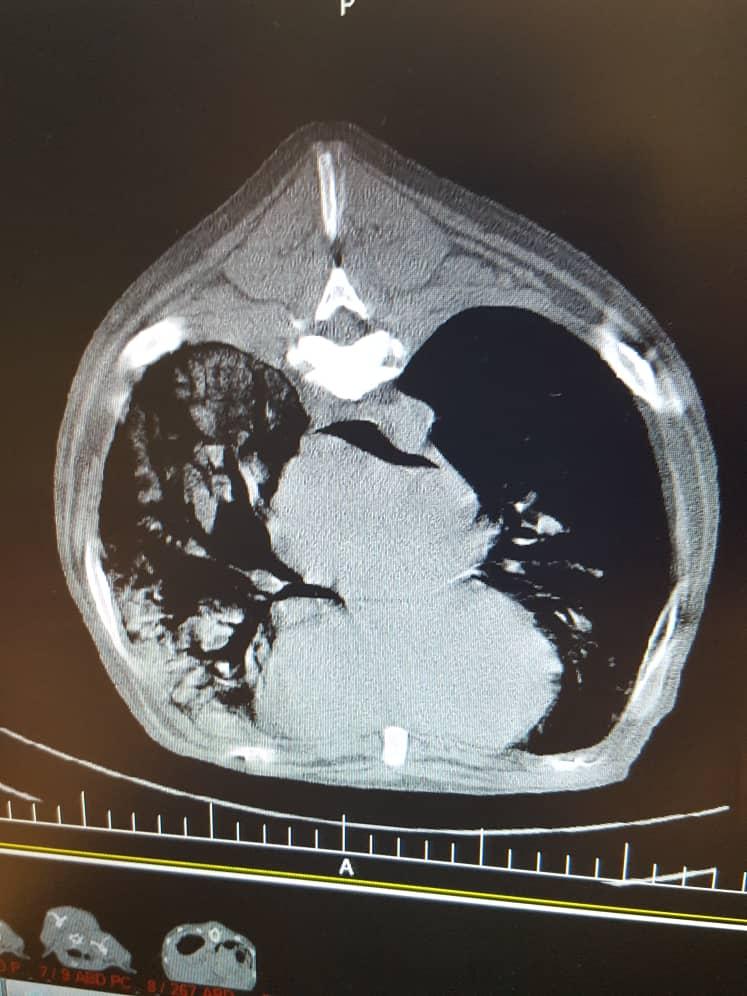

I have a 10 yo AKC registered labrador who currently lives in overseas. He has developed severe dysphagia, barrium swallow showed obstruction and CT scan showed large lung tumor. His Vet in overseas says nothing can be done for him. But I want a second opinion from a vet in US please look at the CT and let me know. I only can send 3 images here. But I have more. Thanks

The problem is that you can possibly try to remove the tumors with surgery. However, your dog is an old dog and the anesthetic risk in a dog with a large lung tumor at this age is great and it is likely that your dog will die during anesthesia. The obstruction can probably be removed, but again the anesthetic risk is great. Recuperation will also be extensive and there is a big chance that your dog's tumors will reoccur before he has even returned to wellbeing from the surgery, should he have survived it. I agree with the veterinarian who diagnosed him (considering what you have reported). You can get a second opinion from an oncologist overseas. They are no worse than the ones here in the US. I am sorry your dog is so ill.